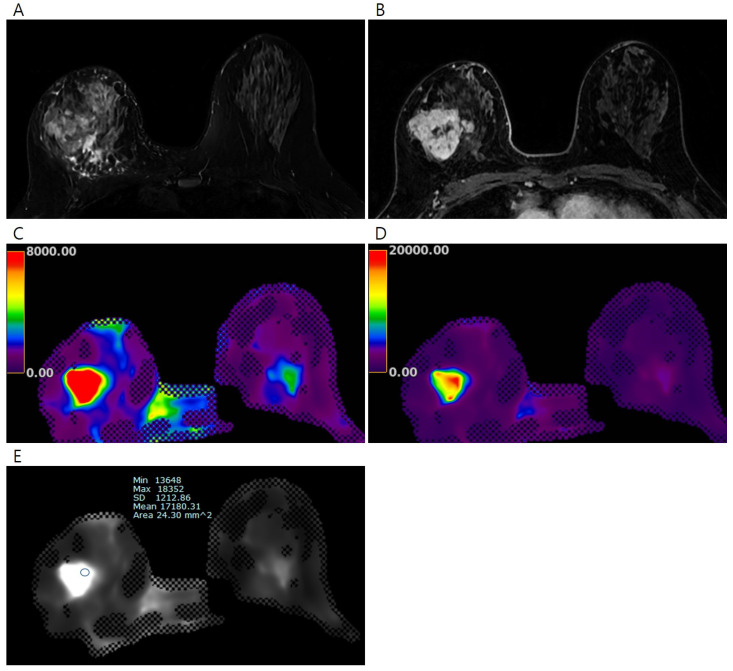

目的:利用磁共振弹性成像(MRE)评估乳腺组织的弹性值,探讨浸润性乳腺癌弹性值与预后因素和新辅助全身治疗(NST)的病理反应之间的关系。方法:前瞻性纳入57例超声检查直径大于2cm的浸润性乳腺癌患者(平均年龄54.1岁)。采用商用声学驱动器通过MRE测量浸润性乳腺癌、正常纤维腺组织和正常脂肪组织的弹性值(平均值、最小值和最大值)并进行比较。根据术前接受NST的患者的预后因素和病理反应比较乳腺癌的弹性值。采用受试者工作曲线分析来评价弹性值对病理反应的预测作用。结果:57例浸润性乳腺癌患者的平均弹性值明显高于正常纤维腺组织和正常脂肪组织(7.90±5.80 kPa vs. 2.54±0.80 kPa vs. 1.32±0.33 kPa, ps均< 0.001)。大直径浸润性乳腺癌(> ~ 4cm)的平均弹性值明显高于小直径肿瘤(≤4cm)(11.65±7.22 kPa vs. 5.87±3.58 kPa, p = 0.002)。在24例接受NST治疗的患者中,病理完全缓解(pCR)组和非pCR组的平均、最小和最大弹性值差异有统计学意义(均p < 0.05)。对于平均弹性值,区分pCR组和非pCR组的曲线下面积为0.880(95%可信区间为0.682,0.976;P < 0.001)。结论:通过乳腺MRE测量的浸润性乳腺癌的弹性值与肿瘤大小呈正相关,具有预测NST患者治疗反应的潜力。

Objectives: To assess the elasticity values in breast tissues using magnetic resonance elastography (MRE) and examine the association between elasticity values of invasive breast cancer with prognostic factors and the pathologic response to neoadjuvant systemic therapy (NST). Methods: A total of 57 patients (mean age, 54.1 years) with invasive breast cancers larger than 2 cm in diameter on ultrasound were prospectively enrolled. The elasticity values (mean, minimum, and maximum) of invasive breast cancers, normal fibroglandular tissues, and normal fat tissues were measured via MRE using a commercially available acoustic driver and compared. Elasticity values of breast cancers were compared according to prognostic factors and pathologic responses in patients who received NST before surgery. Receiver operating curve analysis was performed to evaluate the predictive efficacy of elasticity values in terms of pathological response. Results: Among the 57 patients, the mean elasticity value of invasive breast cancers was significantly higher than that of normal fibroglandular tissue and normal fat tissue (7.90 ± 5.80 kPa vs. 2.54 ± 0.80 kPa vs. 1.32 ± 0.33 kPa, all ps < 0.001). Invasive breast cancers with a large diameter (>4 cm) exhibited significantly higher mean elasticity values relative to tumors with a small diameter (≤4 cm) (11.65 ± 7.22 kPa vs. 5.87 ± 3.58 kPa, p = 0.002). Among 24 patients who received NST, mean, minimum, and maximum elasticity values significantly differed between the pathologic complete response (pCR) and non-pCR groups (all ps < 0.05). For the mean elasticity value, the area under the curve value for distinguishing pCR and non-pCR groups was 0.880 (95% confidence interval, 0.682, 0.976; p < 0.001). Conclusions: The elasticity values of invasive breast cancers measured via breast MRE showed a positive correlation with tumor size and showed potential in predicting the therapeutic response in patients receiving NST.